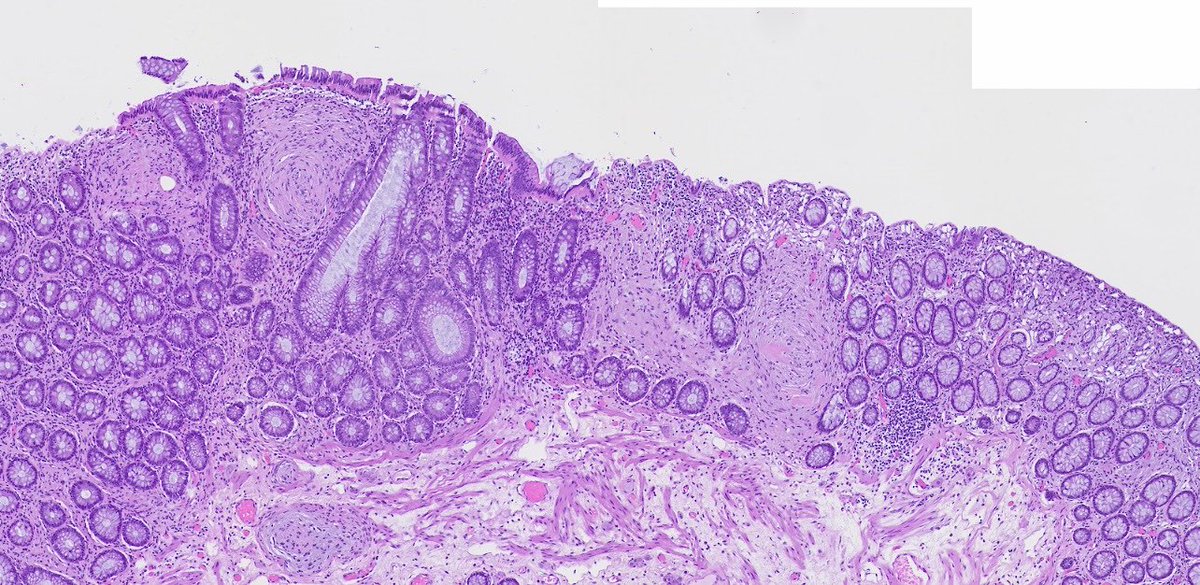

Appendicitis with an incidental serrated epithelial proliferation. The preferred terminology is "serrated polyp" rather than SSL as they have different genetics to their colonic counterparts. NB this is not LAMN as the muscularis mucosae is intact @Pathoutlines @RaulSGonzalezMD